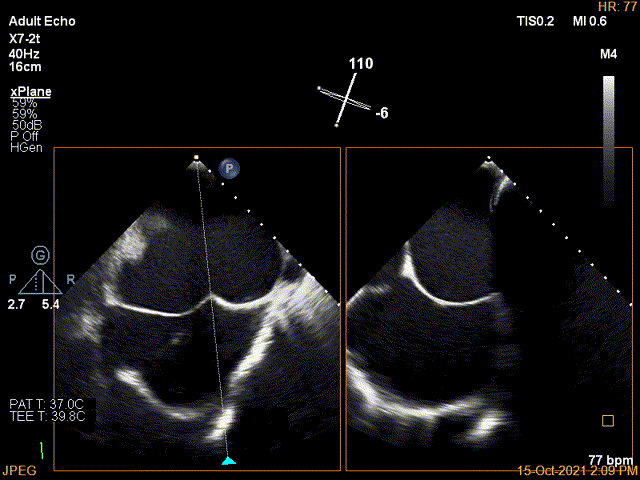

X-plane:下夹子尝试先捕获1区脱垂瓣叶

3D证实夹子内侧残余Flail

3D-color证实残余分流主要位于内侧2区